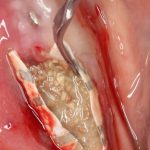

Даже если вы делаете операцию над лункой удалённого зуба — здесь вам особенно важно сохранять контроль над дном, ибо длительно существующий периапикальный процесс нередко ведёт к образованию спаек, и риск перфорации очень высок. А иногда бывает и такое, что дно верхнечелюстной пазухи находится ниже апикальных частей лунки. В этом случае можно смело проводить нижнюю границу прямо по лункам — ничего страшного в этом нет, а хороший обзор в таких случаях гораздо важнее.